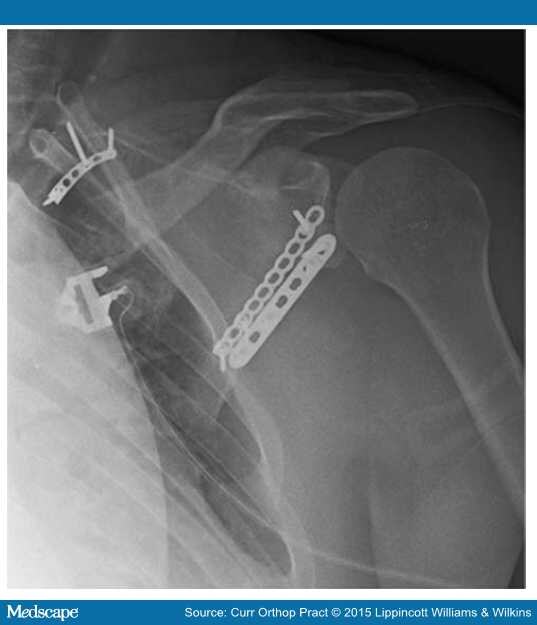

Open Reduction and Plating of Scapula and Acromion Fracture With Scapula Fracture Judet Approach The modified judet approach avoids detachment of the deltoid muscle and gains almost the same. Exposure of the body and articular segment of the scapula is based on the extensile judet approach. Although universally accepted as a helpful and effective. A fairly limited approach to the shoulder, allowing little anterior exposure. Scapula fractures are uncommon fractures to the shoulder girdle. Scapula Fracture Judet Approach.

From journals.lww.com